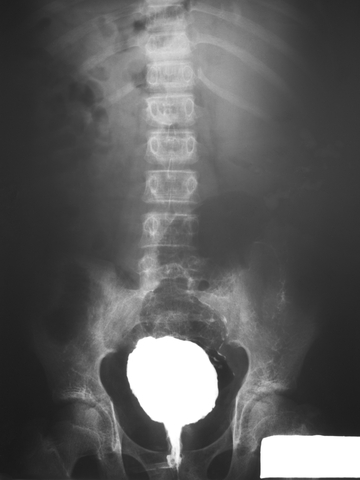

Contrast media is commonly used to enhance the quality of advanced images such as CT scans and magnetic resonance imaging (MRI). More advanced than a typical X-ray, these images can depict bone as well as blood vessels, organs and muscle. Producing a highly detailed image, these technologies are often used to diagnose common conditions, detect tumors or other abnormalities and help physicians prepare for surgeries. An estimated 50 million imaging exams are conducted with contrast media each year.